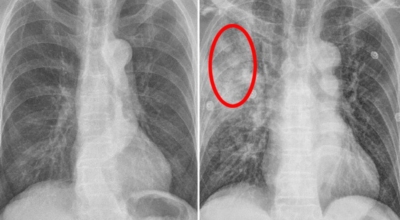

인체가 순조롭게 기능을 발휘하려면 폐 건강이 필수다. 폐는 인체가 효율적으로 움직이는 데 있어 바퀴 안에 있는 톱니 같은 역할을 하기 때문이예요. 산소를 제공하는 폐 기능이 감소하게되면 폐렴이나, 만성 폐쇄성 폐질환(COPD), 천식 등 정도가 심한 호흡기 질환 발생 위험이 증가해요. 이런 질병들은 폐를 공격해 숨쉬기 힘들게 만들어요.

특별히 현대 사회에서 폐는 가장 시달리는 장기 중 한 종류다. 가지가지 공해 성분으로 오염된 공기에 미세 먼지, 황사까지 더하면 폐 안쪽에 있는 허파꽈리(폐포)부터 정도가 심한 훼손을 입습니다. 따라서 폐 건강을 증진시키기 위하여는 폐에 좋은 음식을 섭취할 필요가 있어요.